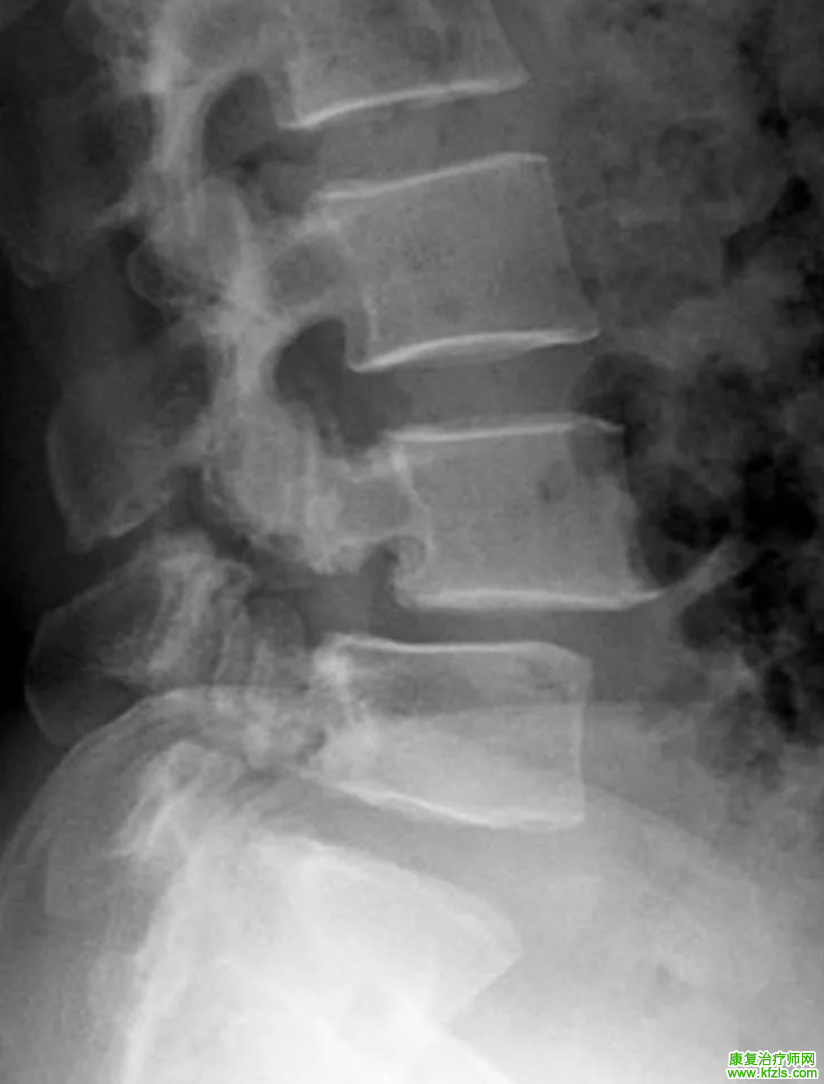

Ⅱ度

腰4椎弓峡部裂、腰4椎体向前 II度滑脱